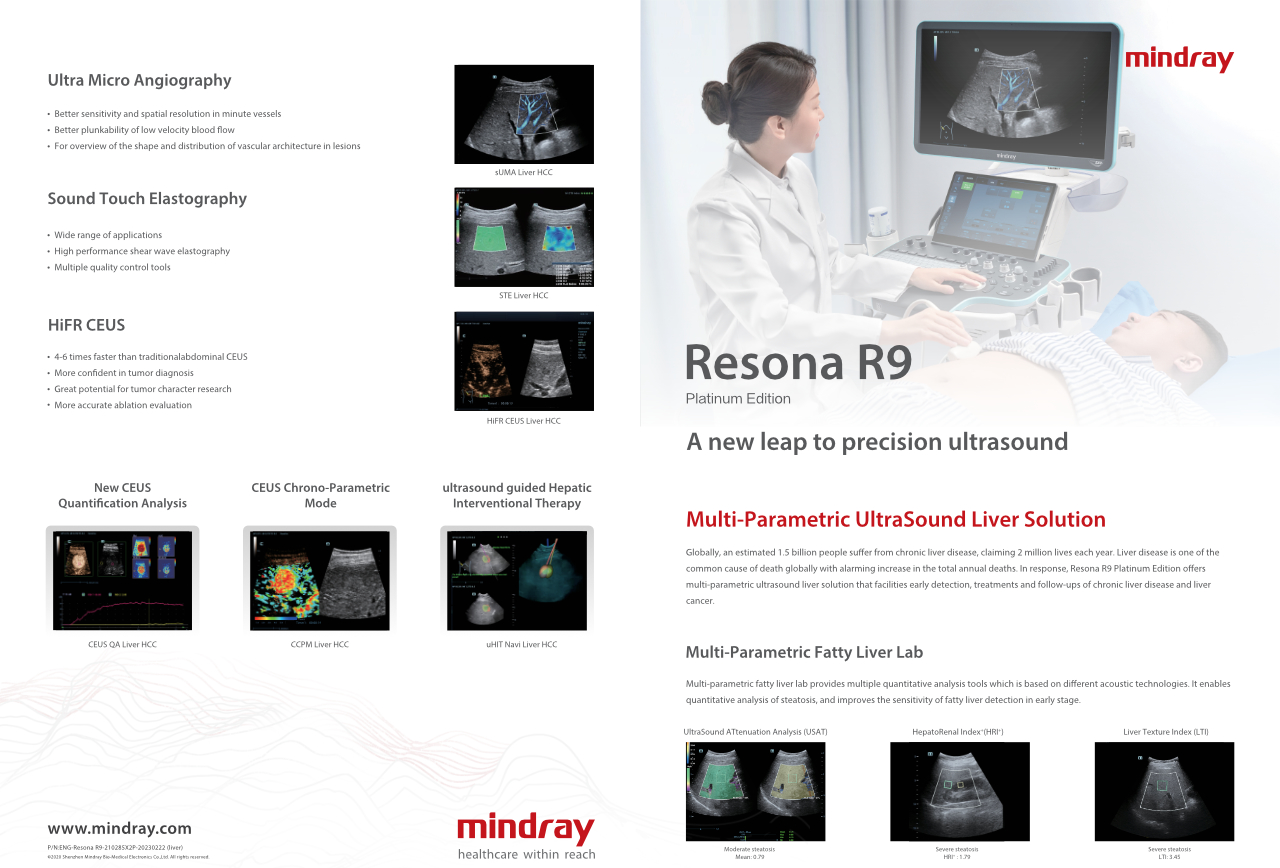

Com que clareza vocĂȘ consegue ver um fĂgado?

Para les?es hepĂĄticas focais, tais como hemangioma ou c?ncer hepĂĄtico, a imagem de contraste por ultrassom desempenha um papel significativo. A tecnologia de imagem por contraste UWN+ n?o linear ultralarga pode ajudar a obter melhor penetra??o e maior rela??o contraste-tecido, com menor MI e maior observa??o do tempo de perfus?o.